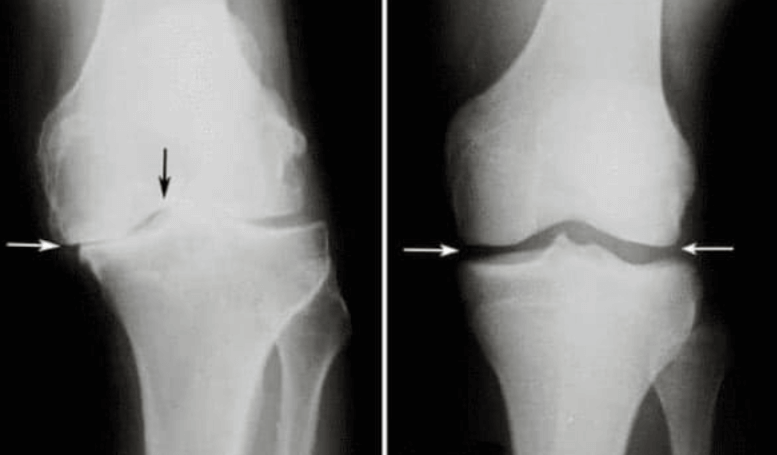

Martin Repko: Hlavní příčinou problémů s klouby a páteří je nedostatečná produkce kloubní mazi.

Kloubní maz totiž funguje jako přirozené mazivo. Když není jeho dostatek, klouby se opotřebovávají a poškozují. Nejvíce postihnutá jsou kolena, prsty, lokty a páteř.

Martin Repko: Hlavní komplikace patologie kloubů zahrnují změnu tvaru kloubu, výrazné omezení pohybu a ztuhlost, která kloub zcela imobilizuje, často v nesprávné pozici.

V případě neúplného ohybu a natažení kloubů se mění osy končetin, podél kterých se rozkládá hlavní mechanická zátěž těla. V důsledku systematického narušení správné osy končetiny se zvyšuje zatížení ostatních kloubů, což vede k sekundárním degenerativním změnám.

Týká se to především těžkých kloubů: kolenních, kyčelních a kotníkových.